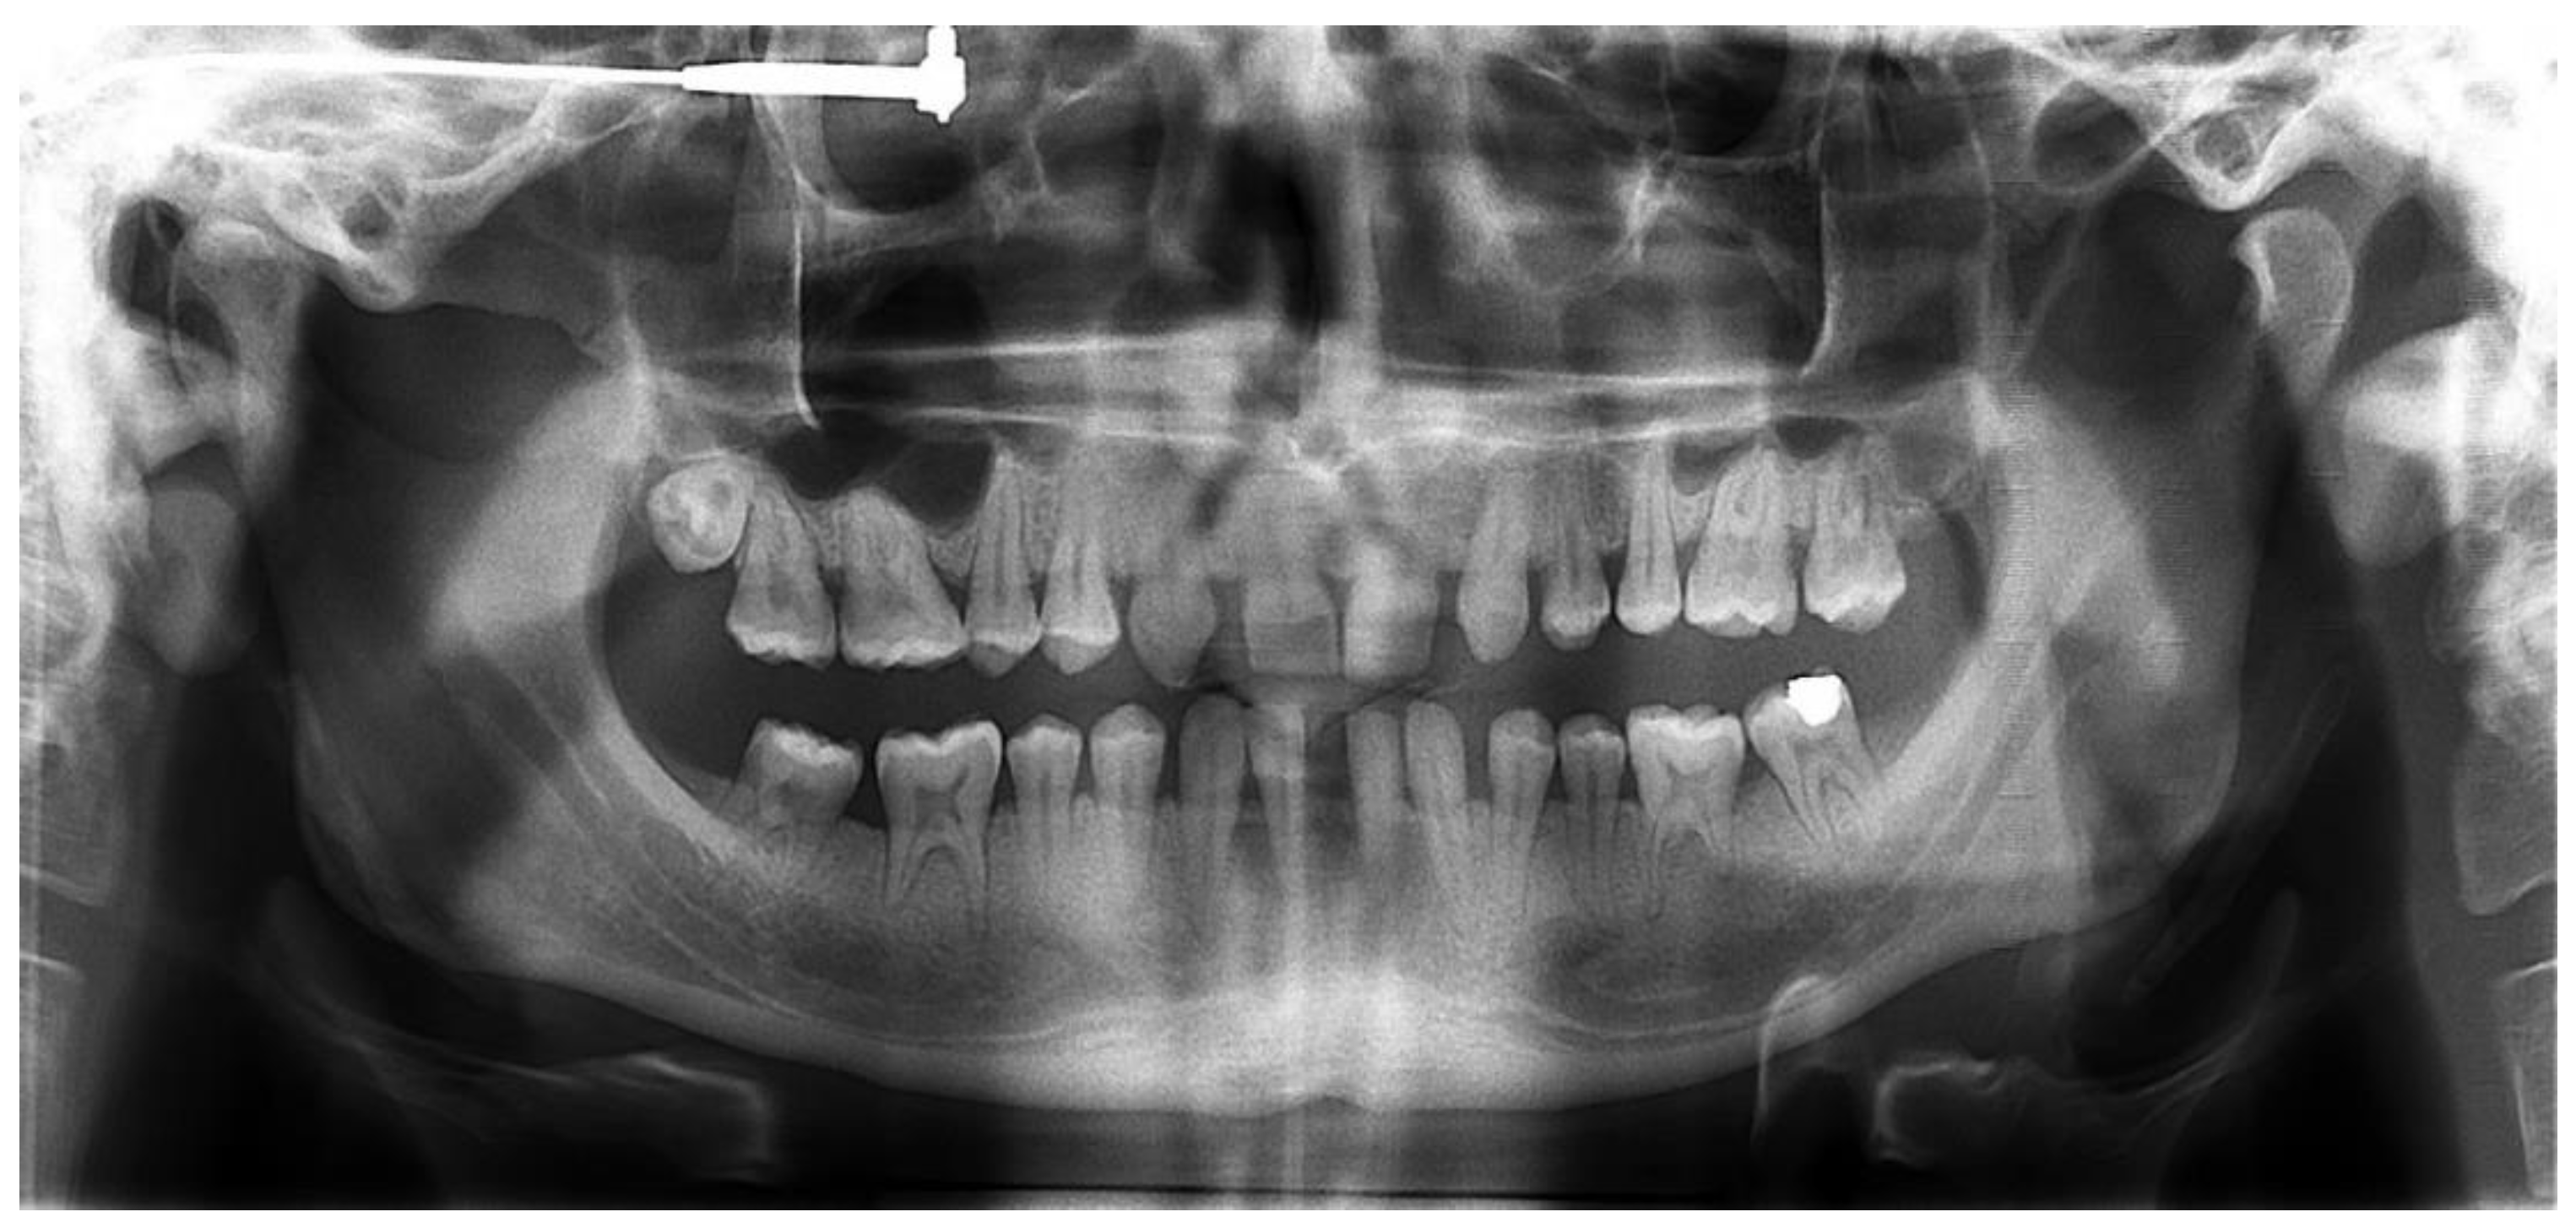

First, alginate impressions were made to obtain diagnostic casts. These casts were mounted in an articulator in order to analyze the case. Face photos and intraoral views were taken and are presented in Figure 1 and Figure 2. The orthopantomogram shown in Figure 3 was realized.

Figure 3.

Orthopantomogram of the patient’s initial dental condition in February 2021.

Endobuccal clinical assessment revealed dental agenesis of the upper left and right lateral incisors and lower left and right central incisors, generalized small teeth size, infiltrated maxillary grooves, and an amalgam restoration on the occlusal surface of the lower left second molar. Occlusal analysis showed complete overbite, a left unilateral articular inversion on the two upper left molars, an Angle Class I canine and molar on the right side and an Angle Class II canine and molar on the left side. In addition, the anterior overhang is reduced, so the patient is in class II division 2.

The radiological examination revealed voluminous dental pulps, apical root resorptions on the lower molars and the absence of the upper left third molar and the two lower third molars.